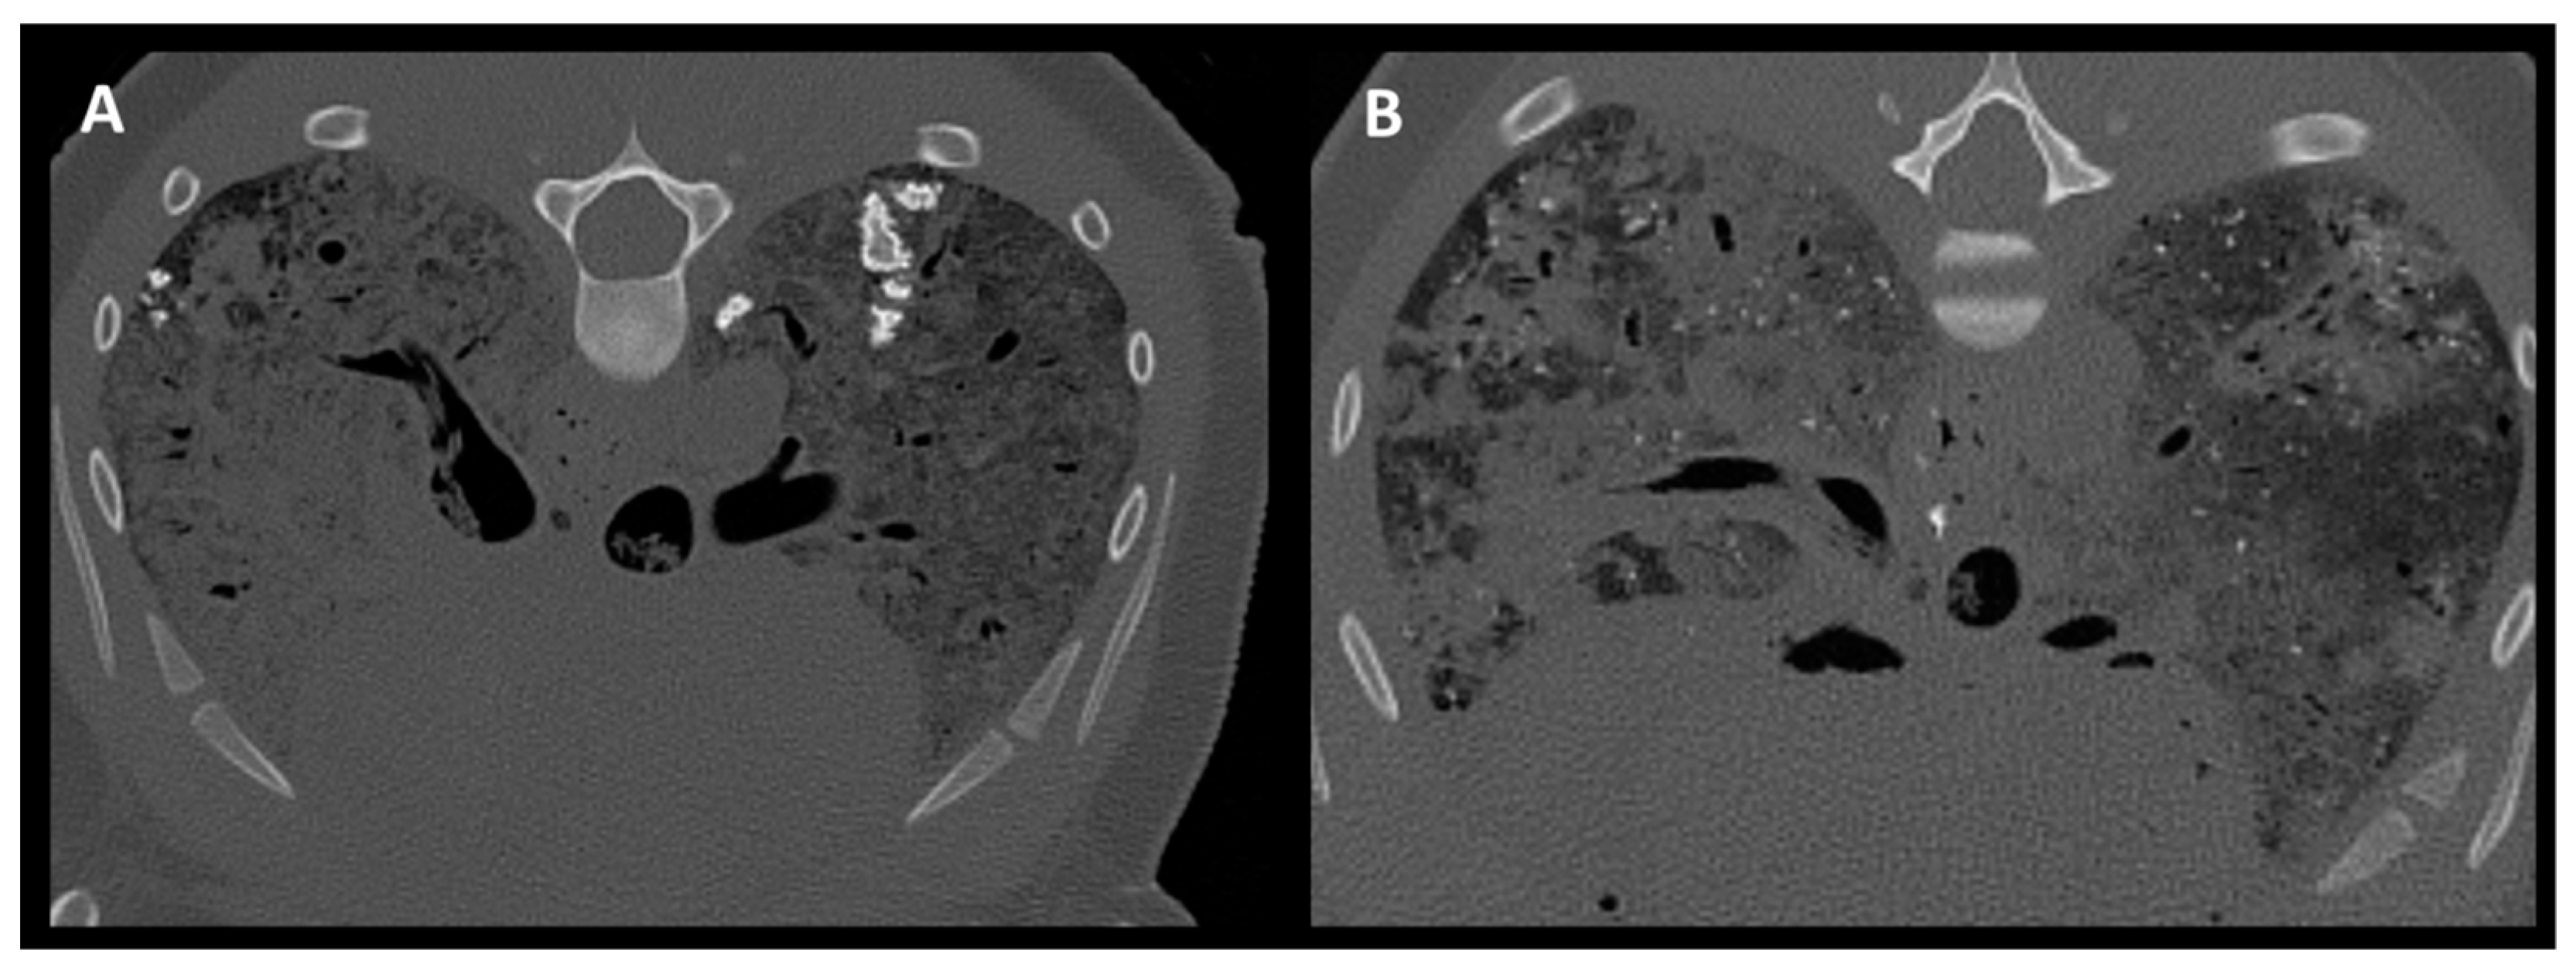

2.4. Tracheobronchial Changes

3.3. Tracheobronchial Changes